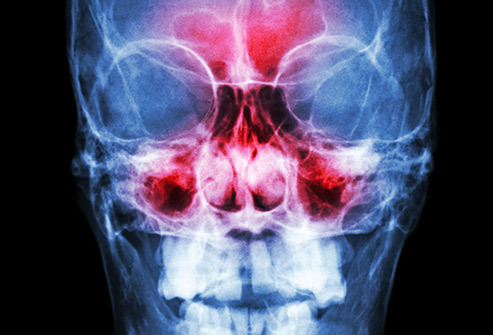

В ваши пазухи опухли

Простая простуда может воспалить полости позади ваших скул и лба. Отек может вызвать боль, которая усиливается при наклоне. Может трудно дышать, потому что слизь, которая может стать густой и желтой или зеленой, не позволяет дышать свободно. Лекарства, отпускаемые без рецепта, часто могут помочь вам справиться с этим. Нет необходимости посещать врача, если симптомы не ухудшаются.